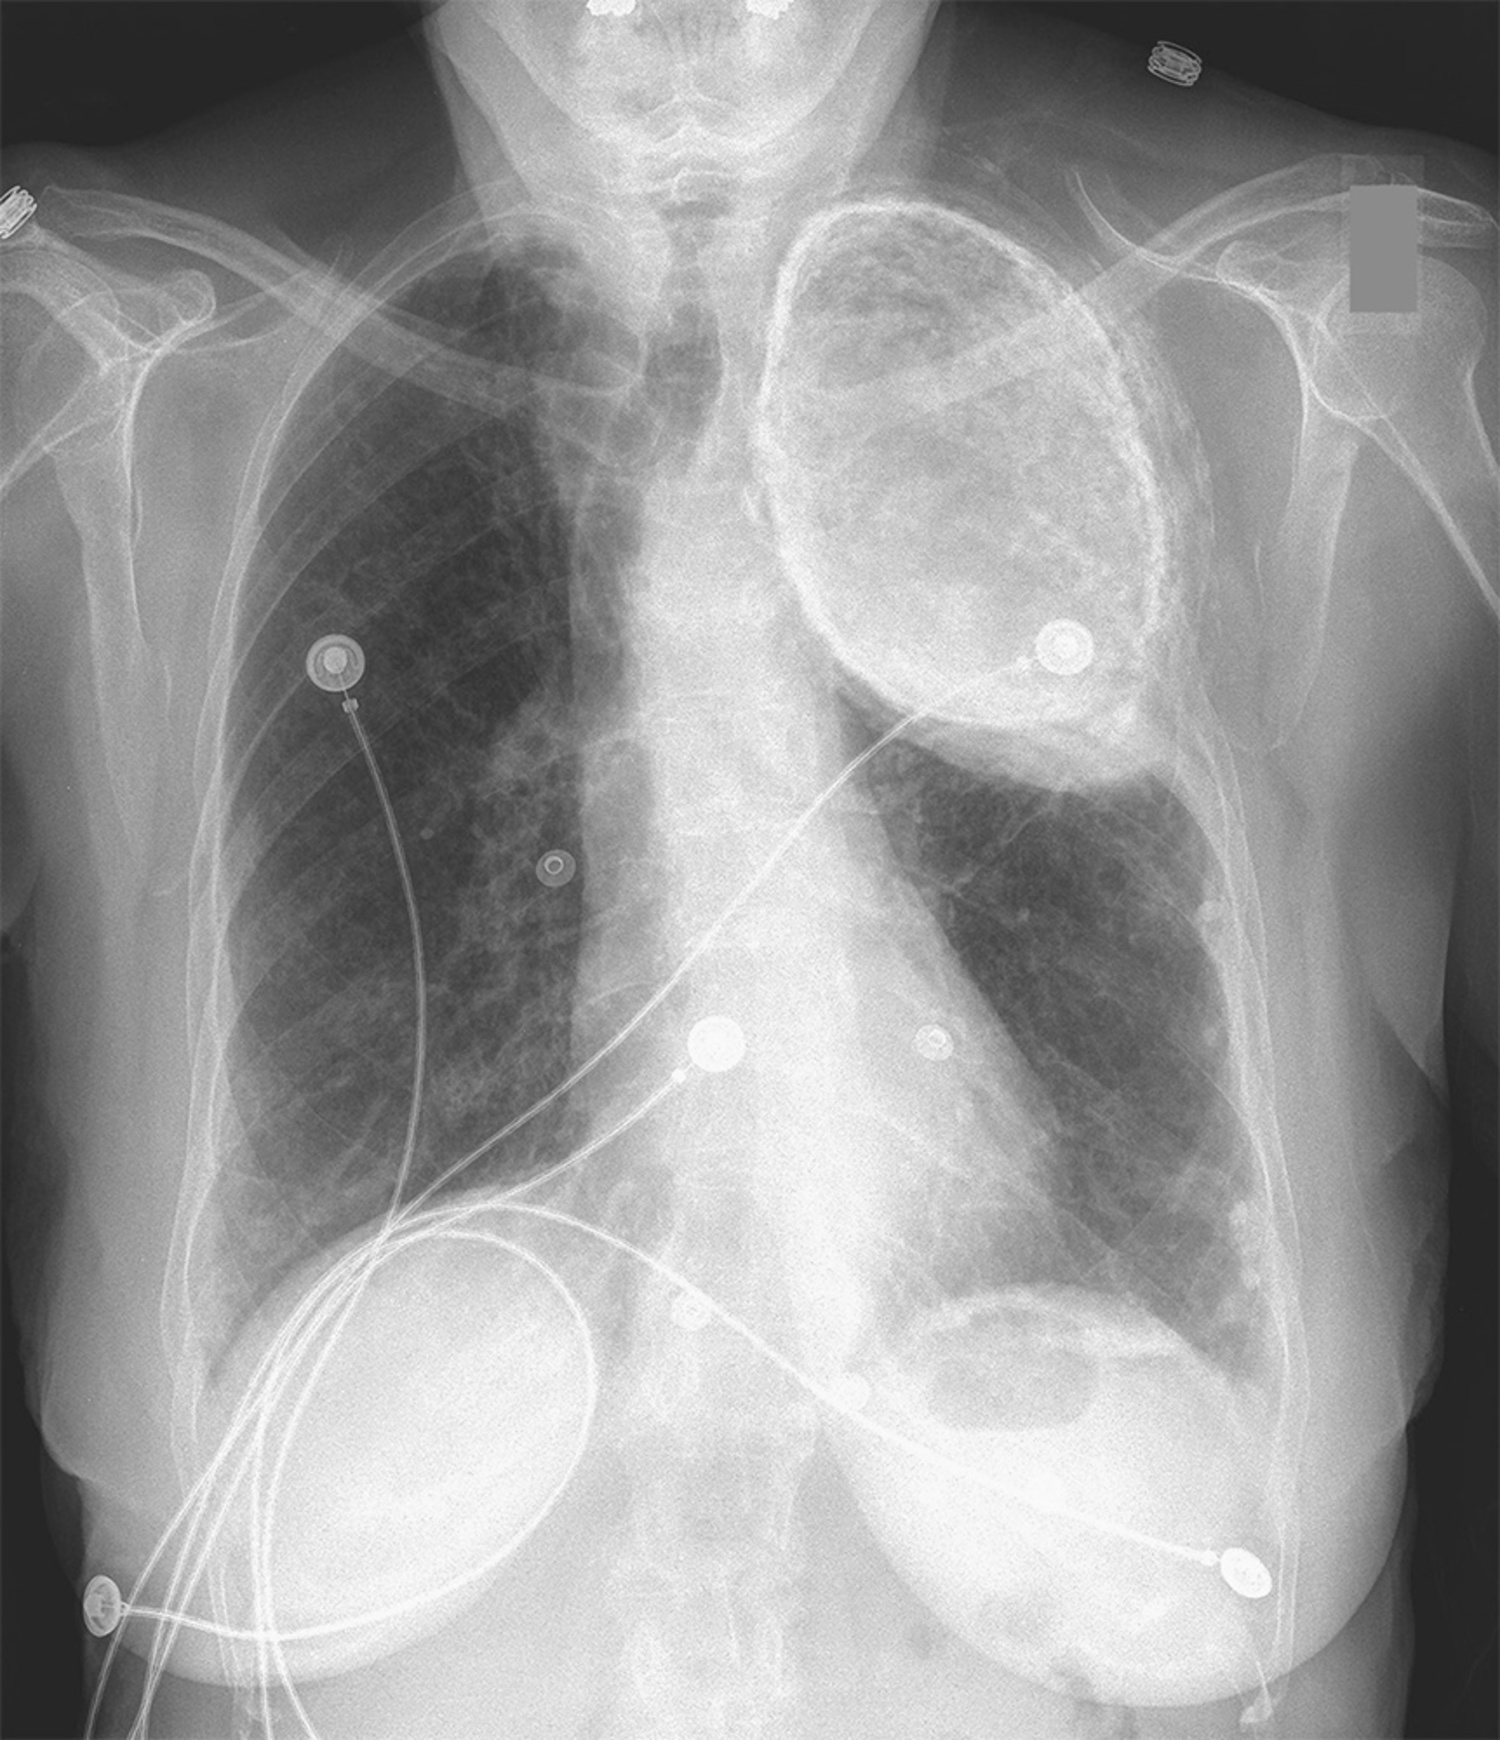

Name of this condition in an asymptomatic woman

Olethorax